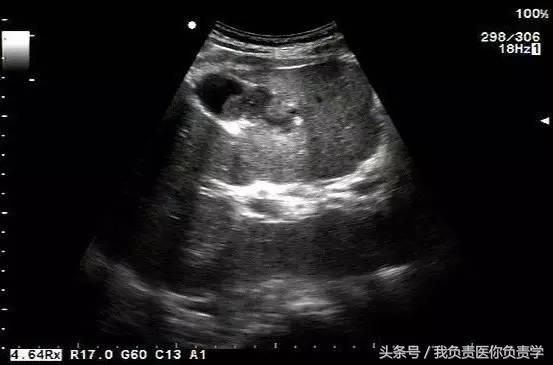

图1示胆囊体积明显增大,内部透声差

图2示胆囊周围可见液性暗区分布

图3-图6示胆囊壁局部回声中断,探头加压及松开时CDFI可见红色及蓝色多普勒信号